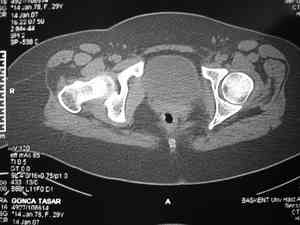

Dear group,30 years age female MVA front seat, head trauma + post column left acetabular fracture, 2.5 weeks skeletal traction. She is now conscious but still confused without any surgical treatment for brain edema.

Latest X rays and CAT is attached.Fracture within first 1.5 cm from the weight bearing dome, although AP and Obtrator oblique good, iliac oblique view reveals some displacement.I'm not sure that nonsurgical treatment will be OKHüseyin DemirorsBaskent UniversityDept of Orthopedics and TravmatologyAnkara TURKEY

My vote, given the amount of displacement on the iliac oblique and CT scan, would be for ORIF thru a posterior approach ASAP - these get pretty tough

I may get beat up for this, but I see very little displacement that concerns me on the CT. The radiograph is more concerning. I suspect it could look better, and the gap made smaller on CT. Not sure if it will affect outcome. I might give it a shot and try to see what could be done.